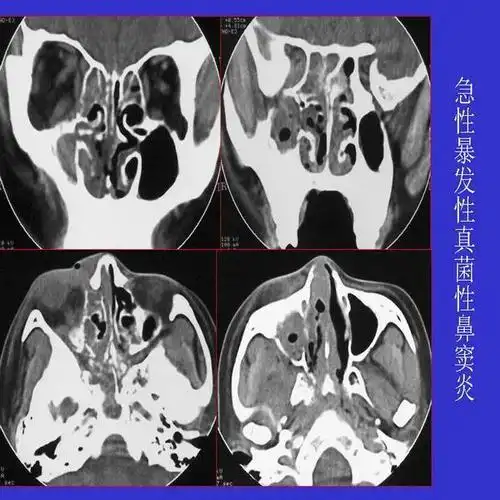

真菌性鼻窦炎影像学诊断